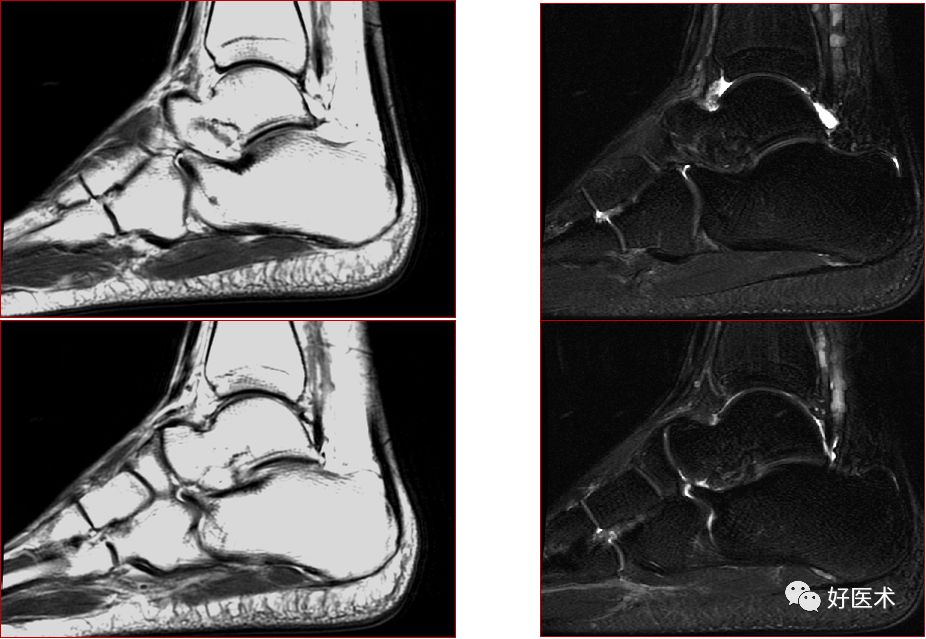

三角骨综合征(距骨三角综合征)

足底腱膜炎(跖腱膜炎)

正常足底腱膜

足底腱膜炎MRI表现

足底腱膜炎:注意跟骨内侧结节的局限性水肿